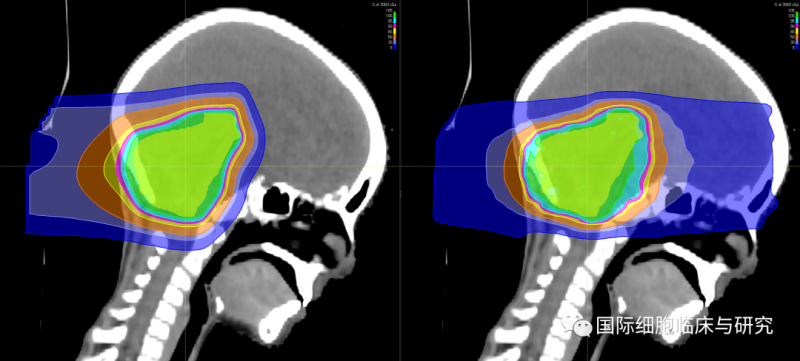

图中左侧为质子疗法的放射剂量分布图像,右侧为光子疗法的放射剂量分布图像;绿色所示区域为目标病灶区域,从红色至蓝色示放射剂量逐渐降低。

我们可以清晰地看到,光子疗法(右)的射线在穿过病灶区域之后仍保持一定的剂量,持续照射至患儿的眼部等部位;而质子疗法(左)的射线在击中病灶区域后照射剂量迅速降低,对于正常组织造成的放射伤害更小。